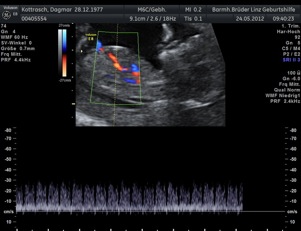

* First Trimester Screening. Messung der Nackentransparenz, Nasenbein, Combined Test (12.-14. SSW) - hier Termin vereinbaren!

d.h. pränataler Ultraschall (Messung der Nackendicke, Organscreening) einerseits, andererseits kann noch eine Untersuchung mittels 4D-Ultraschall durchgeführt werden,